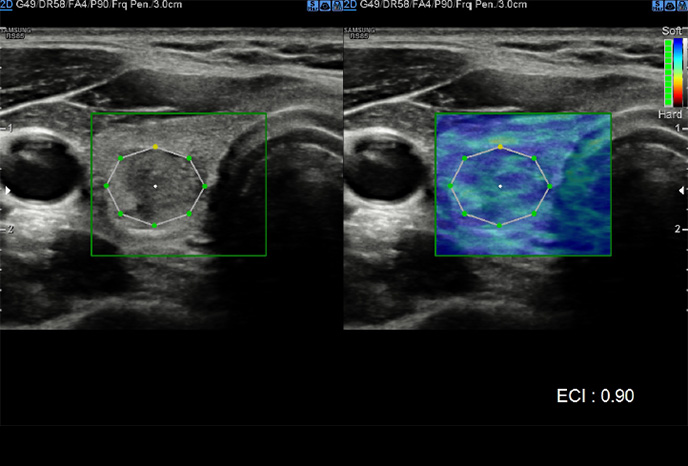

S-Shearwave Imaging ™

Neinvazivní metoda kvantifikace tuhosti tkáně

S-Shearwave Imaging ™ umožňuje neinvazivní hodnocení tuhosti tkáně / lézí v prsu a játrech, poskytnutím pokročilé úrovně diagnostických informací. Barevně mapovaný elastogram, kvantitativní měření (inkPa nebo m / s), možnost duálního zobrazení a uživatelem volitelné funkce ROI (pozice a velikost) jsou obzvláště užitečné pro přesnou diagnostiku onemocnění prsu a jater.